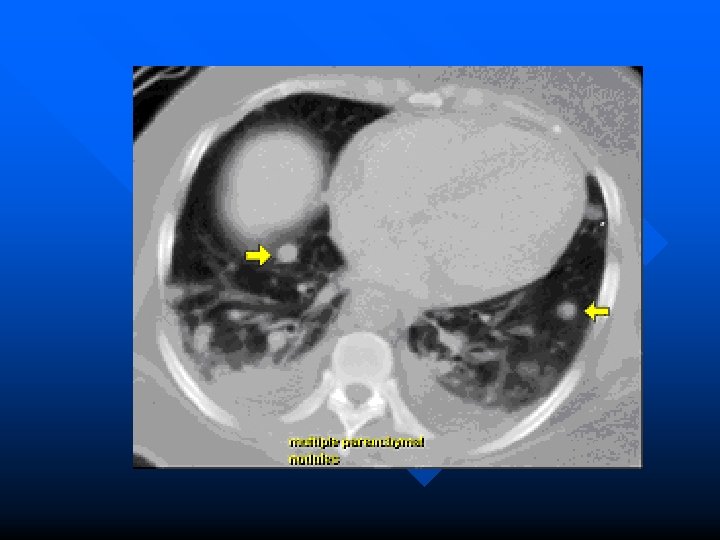

Metastatic tumors Most pulmonary metastases genitourinary and gastrointestinal system. n Hematogenous metastasis Discrete and circumscribed Miliary or snow strom appearance indicated rapid growth. n Lymphatic permeation Mediastinum and its nodes are the first line with this type of spread. n Massive pleural effusion. n